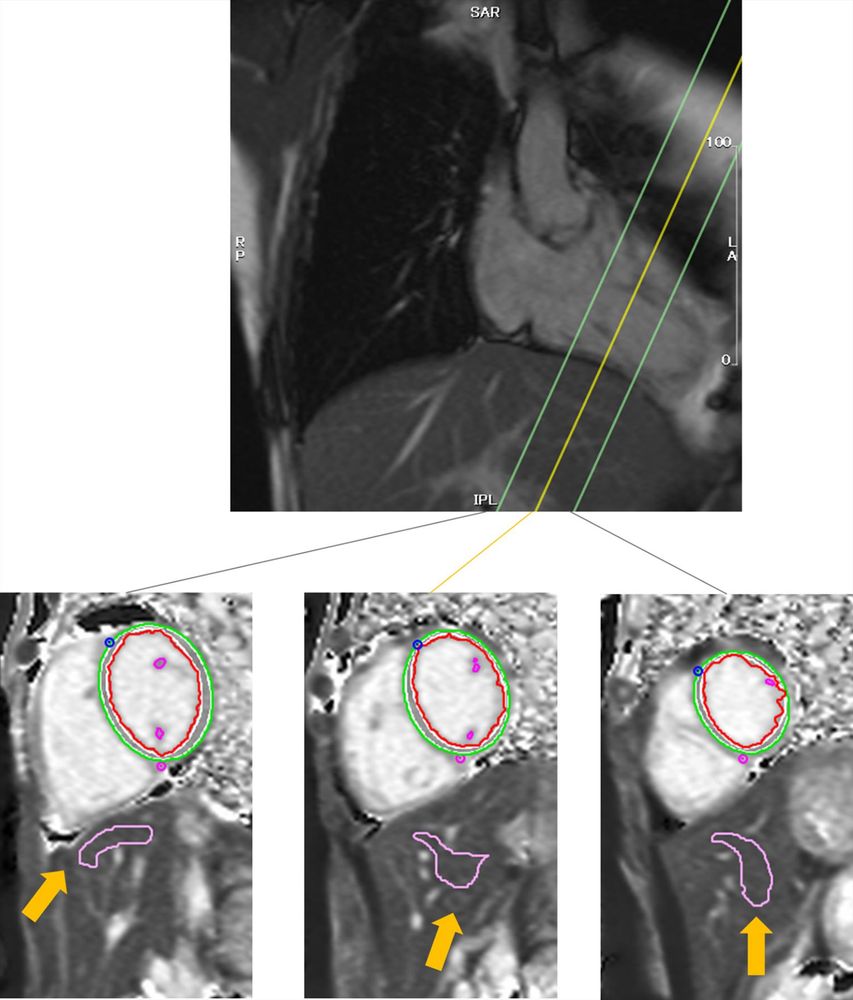

🫀 Paradigm-shifting: MI size & peri-infarction edema not major diastolic impairment determinants post-AMI at #IJCVI!

The size of myocardial infarction and peri-infarction edema are not major determinants of diastolic impairment after acute myocardial infarction

The International Journal of Cardiovascular Imaging - To study the relationship between myocardial infarction size (IS), myocardial edema, and diastolic dysfunction after acute myocardial...